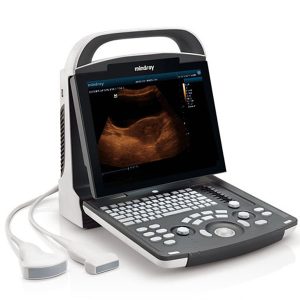

Mindray DP 30 Portable Ultrasound Machine

300,000.00৳ Add to cartRated 0 out of 5 -

Portable Ultrasound Device Mindray DP 15 Power

250,000.00৳ Add to cartRated 0 out of 5 -